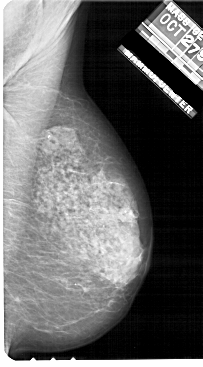

A_1722_1.RIGHT_MLO

LEFT_MLO LINES 5491 PIXELS_PER_LINE 3091 BITS_PER_PIXEL 12 RESOLUTION 43.5 OVERLAY